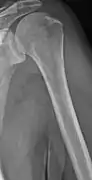

The diagnostic examination of a person with suspected multiple myeloma typically includes a skeletal survey. This is a series of X-rays of the skull, axial skeleton, and proximal long bones. Myeloma activity sometimes appears as "lytic lesions" (with local disappearance of normal bone due to resorption). And on the skull X-ray as "punched-out lesions" (pepper-pot skull). Lesions may also be sclerotic, which is seen as radiodense.[47] Overall, the radiodensity of myeloma is between −30 and 120 Hounsfield units (HU).[48] Magnetic resonance imaging is more sensitive than simple X-rays in the detection of lytic lesions, and may supersede a skeletal survey, especially when vertebral disease is suspected. Occasionally, a CT scan is performed to measure the size of soft-tissue plasmacytomas. Bone scans are typically not of any additional value in the workup of people with myeloma (no new bone formation; lytic lesions not well visualized on bone scan).

Multiple myeloma in the upper arm

Humerus with multiple myeloma lesions

Same humerus before, with just subtle lesions